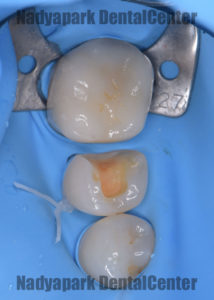

レントゲン写真撮影の結果、右下の奥歯の虫歯が進行していることが分かったので虫歯を除去し、型取りをしてからラバーダム装着下でセラミックの詰め物を装着しました。

ラバーダムの使用には以下のような利点があります。

・歯やセラミックに唾液、血液などの水分の付着を防ぐ

・歯とセラミックの接着力低下の防止

・薬液がお口の中に入らない

・器具や材料の飲み込みを防止

・舌や頬を傷つけない